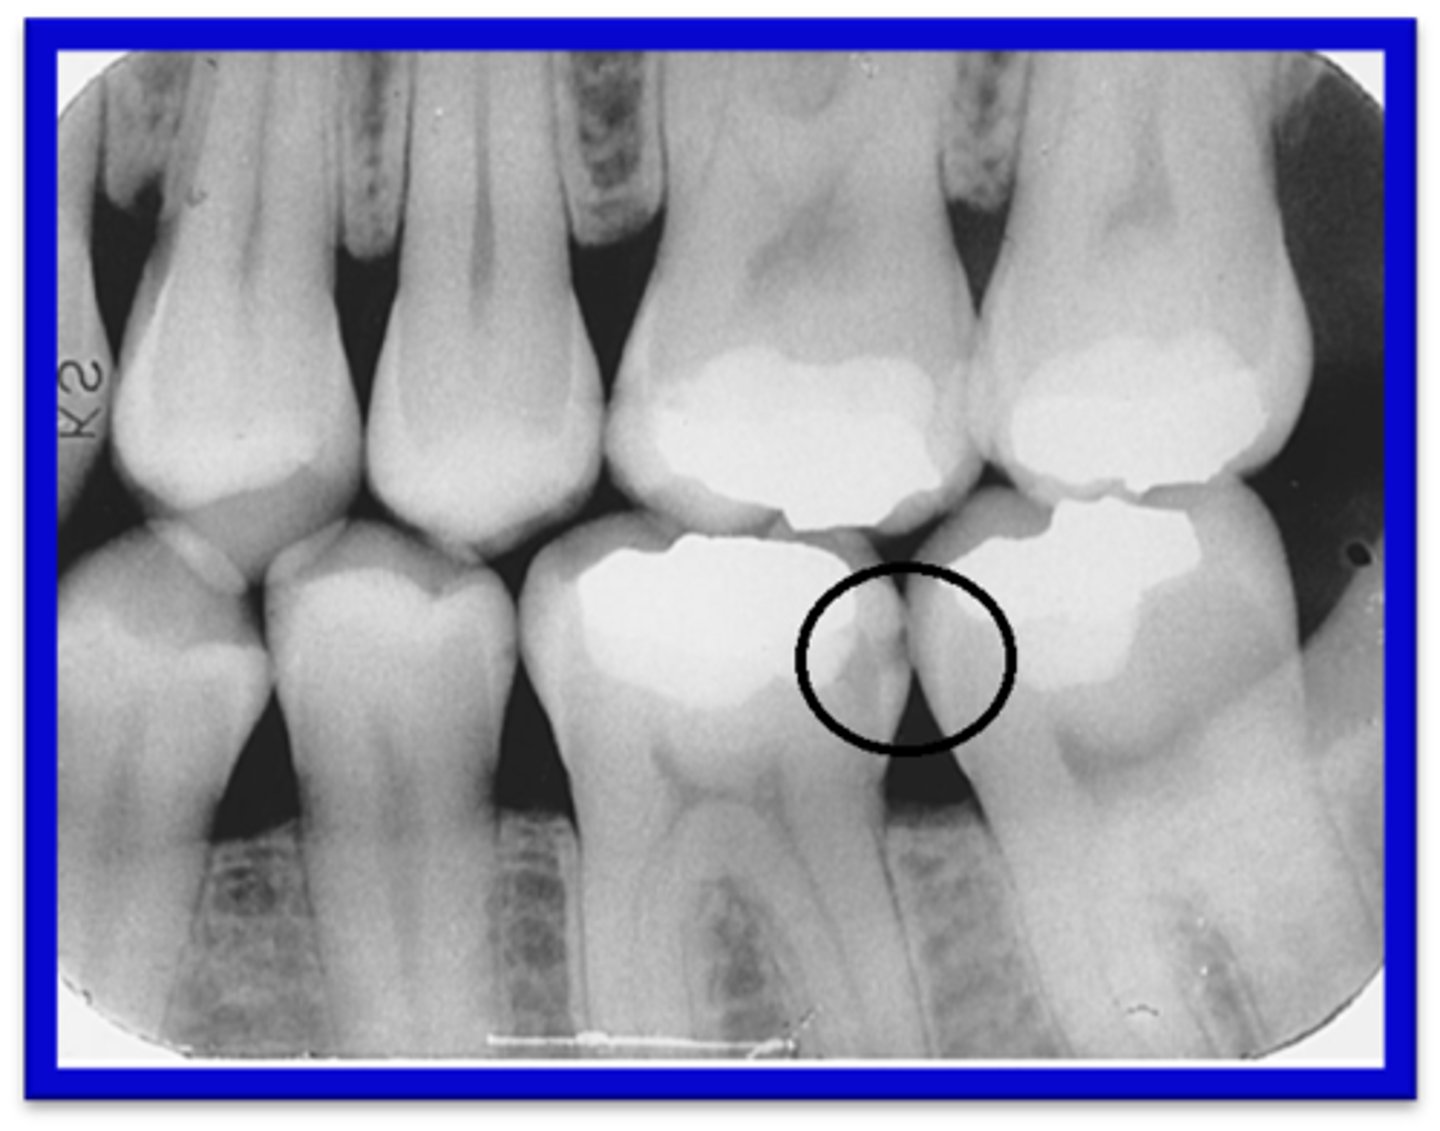

How do Interproximal Caries apppear?

Between 2 adjacent surfaces; typically seen at/just below the contact point. Triangular pattern begins at enamel.

What are Incipient Interproximal Caries?

Extends less than halfway through the thickness of enamel. Class I

What are Moderate Incipient Caries?

Extends more than halfway through enamel but does not involve the DEJ. Class II

What are Advanced Incipient Caries?

Extends to or through the DEJ and into dentin but does not extend into dentin more than half the distance toward the pulp. Enamel and Dentin. Class III